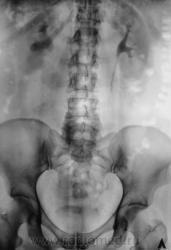

Пациент с клиникой правосторонней почечной колики направлен на рентгенологическое исследование.

В проекции среднего сегмента правой почки тень конкремента. Отсутствие признаков расширения собрательной системы правой почки.

Во-Во! И тени флеболитов в проекции малого таза.